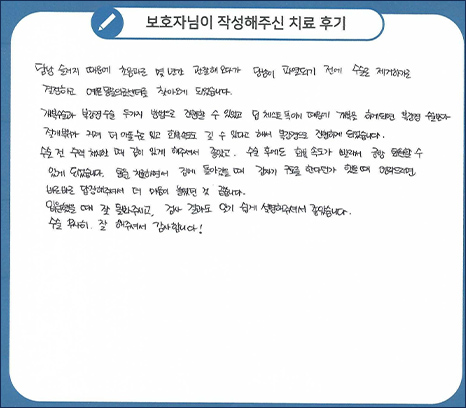

치료 후기

초음파로 몇 년간 관찰해오다가 담낭이 파열되기 전에 수술로 제거하기로 결정하고

예은동물의료센터를 찾아오게 되었습니다. 개복수술과 복강경 수술 두가지 방법으로 진행할 수 있었고

딥 체스트 독이기 때문에 개복을 하게되면 복강경 수술보다 절개부위가 커져 더 아플 수도 있고

회복 속도도 길 수 있다고 해서 복강경으로 진행하게 되었습니다.

수술 전 수액 처치할 때 같이 있게 해주셔서 좋았고, 수술 후에도 회복 속도가 빨라서 금방 퇴원할 수 있게

되었습니다. 통원 치료하면서 집에 돌아갔을 때 갑자기 구토를 한다던가 했을 때 연락드리면 바로바로

답장해주셔서 더 마음이 놓였던 것 같습니다. 입원했을 때 잘 돌봐주시고, 검사 결과도 알기 쉽게

설명해주셔서 좋았습니다. 수술 무사히 잘 해주셔서 감사합니다.